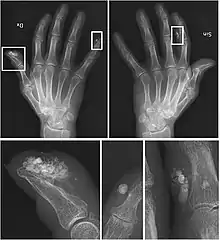

| CREST syndrome (calcinosis and sclerodactyly) | |

CREST causes thickening and tightening of the skin with deposition of calcific nodules ("calcinosis").

Though it is the most easily recognizable manifestation, it is not prominent in all patients. Thickening generally only involves the skin of the fingers distal to the metacarpophalangeal joints in CREST. Early in the course of the disease, the skin may appear edematous and inflamed. Eventually, dermal fibroblasts overproduce extracellular matrix leading to increased tissue collagen deposition in the skin. Collagen cross-linking then causes a progressive skin tightening. Digital ischemic ulcers commonly form on the distal fingers in 30–50% of patients.[3]